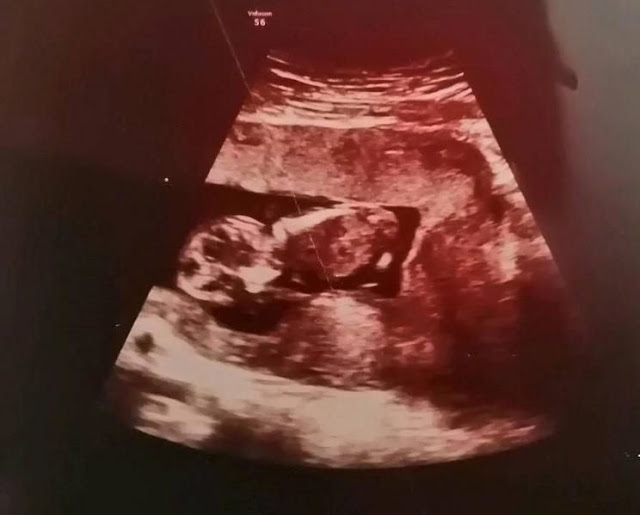

„Problémamentesen zajlott a terhességem, tökéletesen cseperedett a pici. A szülés várható ideje november 5. volt, de október 20-án olyan erős fájdalmakat éreztem, hogy bementem az egyik közeli kórházba. Egész nap a szülőszobán tartottak, vizsgáltak, de végül a rossz véreredményem ellenére hazaküldtek” – idézte fel Andrea. Azt mondta, öt nappal később ismét erős fájdalmakat érzett, és már biztos volt benne, hogy hamarosan megszületik a gyereke, ezért mentőt hívtak, amely elindult vele egy másik kórházba.